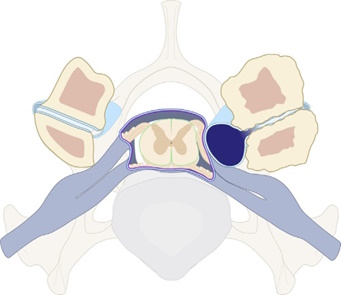

Η οστεοαρθρίτιδα στις αποφυσιακές αρθρώσεις δυο γειτονικών σπονδύλων και κυρίως η επακόλουθη αστάθεια μεταξύ τους, μπορεί να προκαλέσουν την πρόπτωση του αρθρικού υμένα (synovial membrane) διαμέσου ελλείμματος του αρθρικού θυλάκου (joint capsule) και τη δημιουργία παρα-αρθρικής κύστης γεμάτης με αρθρικό υγρό. Στην περίπτωση που η κύστη αυτή διογκωθεί, μπορεί να προκαλέσει εξωσκληρίδια συμπίεση στο ΝΜ.

Κύστη αποφυσιακής άρθρωσης που οφείλεται σε εκφύλιση της άρθρωσης. Η κύστη συμπιέζει την κινητική ρίζα του νωτιαίου νεύρου.